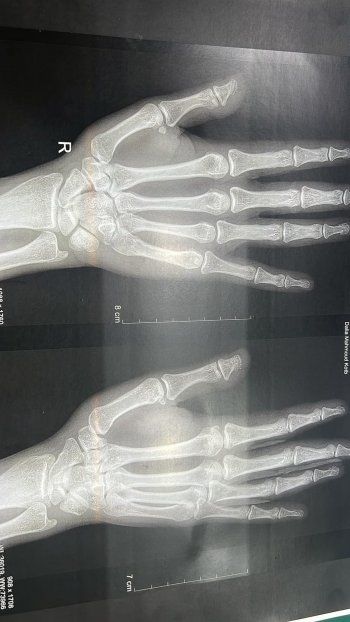

صنعاء - عبدالجليل فارس - تعرضت الممثلة المصرية داليا البحيري لحادثة خلال العرض المسرحي "سيدتي أنا" بعد السقوط على خشبة المسرح، حيث شاركت عبر حسابها الخاص على مواقع التواصل الإجتماعي صور ليديها بعد خضوعها لتصوير أشعة، وعلقت مطمئنةً الجمهور بالقول: "حادثة صغيرة علي ماقسم كده، اختل توازني علي المسرح ووقعت واقعة جامدة حبيتين…نزلت بكل حملي علي ايدي وحسيت برجة جامدة في دماغي…وجع رهيب ايدي ورمت قلت بس انا اتكسرت، كملت العرض الحمد لله وطلعت علي الطوارئ هوب إشاعة هوب الحمد لله مفيش كسر بس في مزق في وتر الإبهام ادي الي ان العضمة اتحركت من مكانها ياختييييي في …كل ده تمام والف حمد والف شكر انها بتيجي علي قد كده".

وأكملت ممازحةً الجمهور بالقول: "المشكلة بقي يا جماعة في اني اكتشفت اني مش عارفة اعمل اي حاجة بمعني اي حاجة من غير الصباع ده…لا عارفة البس ولا اقلع ولا افتح ازازة الماية مش عارفة اشيل حاجة مش عارفة افتح باب العربية ولا أي أكره، مش عارفة اسرح شعري ولا اغسل وشي ولاااا اي حاجة …وكمان مش عارفة اعمل scroll، مش عارفة اعمل like …آه والله ال Like بتوجعني جدا …بس برضو الحمد لله دائمآ وأبدآ …ما يقع الا الشاطر".